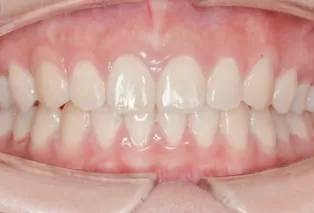

Photos intra-orales

teeth straightening aligners 4

teeth straightening aligners 5

teeth straightening aligners 6

teeth straightening aligners 7

teeth straightening aligners 8